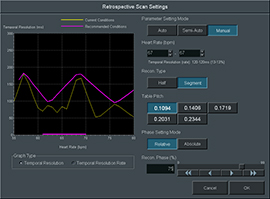

В ходе подготовки системы к сканированию автоматически настраиваются условия оптимального сканирования на основании результатов анализа ритма сердечных сокращений. Все операции просты настолько, что даже число данных в полученных сегментах определяется системой автоматически, исходя из частоты сердечных сокращений во время сканирования.Автоматический контроль дозы

В ходе подготовки системы к сканированию автоматически настраиваются условия оптимального сканирования на основании результатов анализа ритма сердечных сокращений. Все операции просты настолько, что даже число данных в полученных сегментах определяется системой автоматически, исходя из частоты сердечных сокращений во время сканирования.

ECG Editor

Функция правки по электрокардиограммеВ случае аритмии или существенных колебаний ЧСС электрокардиографическая волна и реконструированная фаза могут быть автоматически подвергнуты правке.